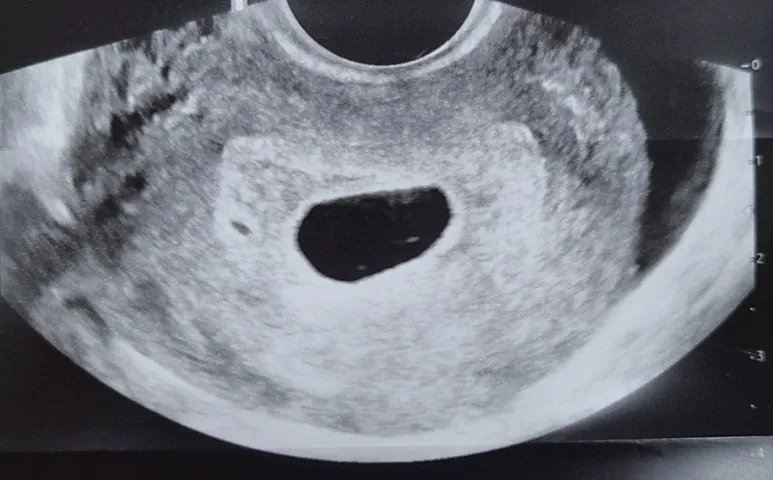

본병원에서 재진료를 보는 날, 역시나 빈 아기집을 다시 마주하게 되었다.